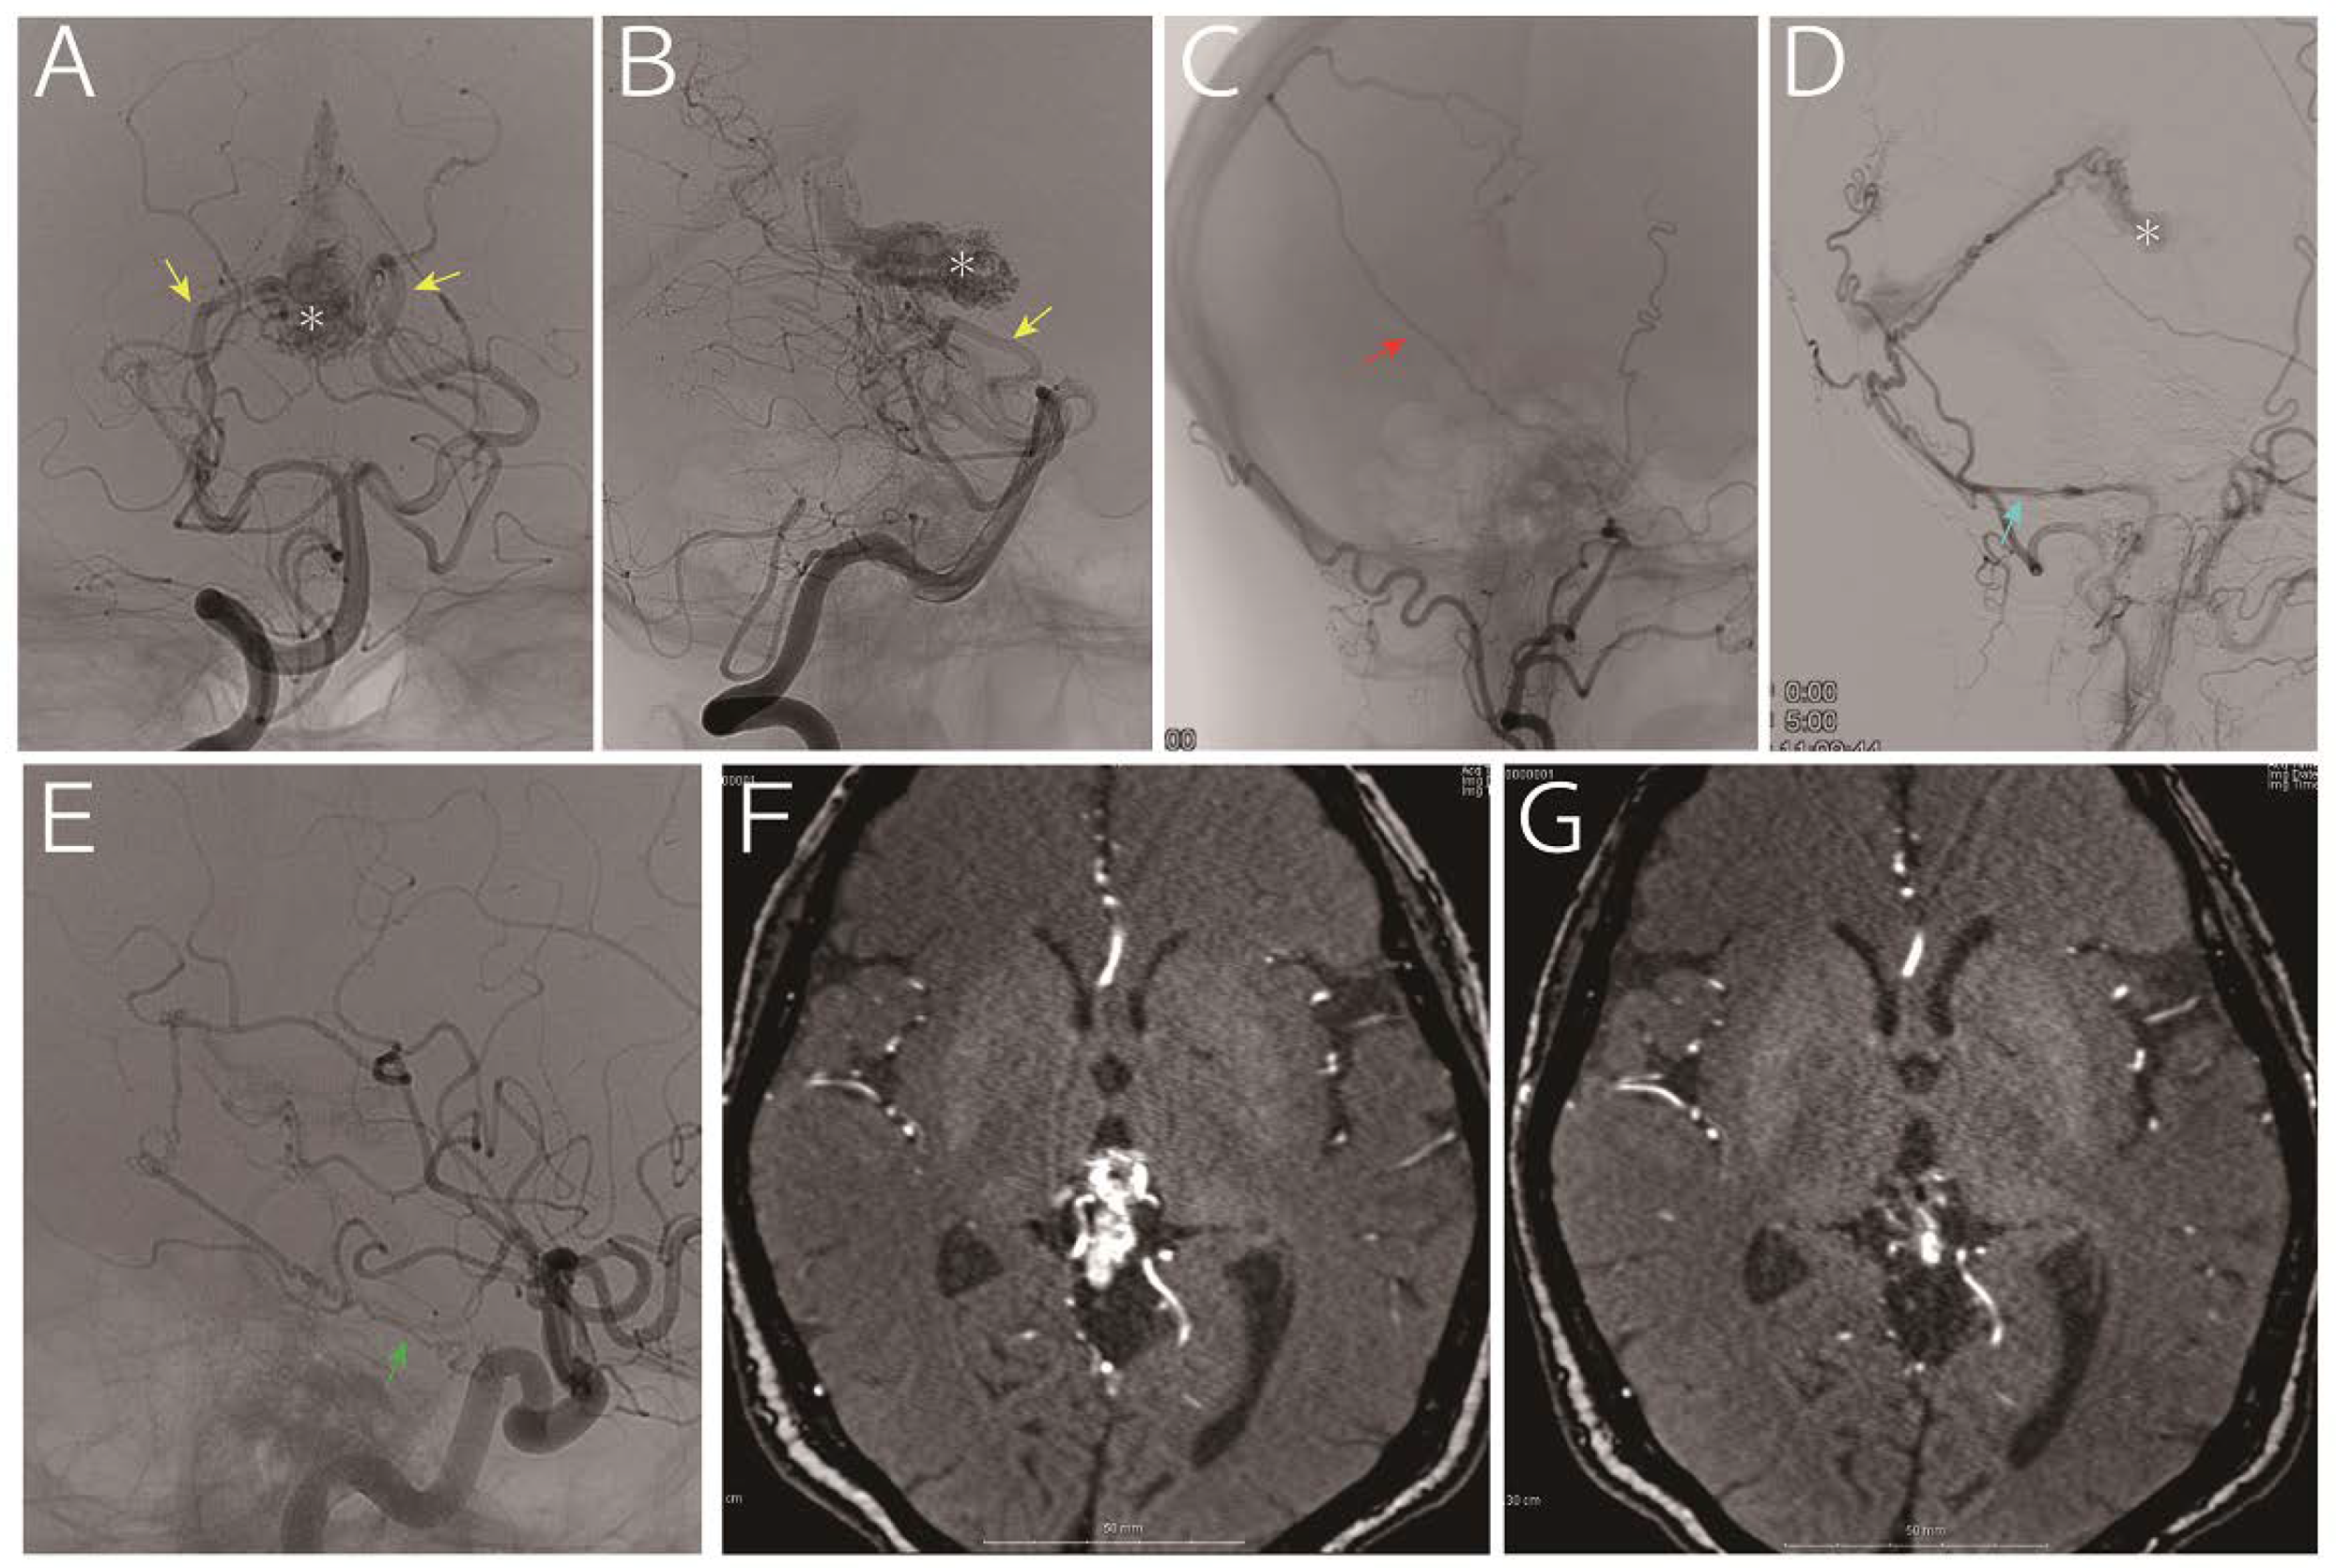

| 1 | 65, M | Hydrocephalus | 9.4 mL | MPChA, BA perforators | Tentorial a., MMA, PMA | VG | 153 mo | Died due to hemorrhage |

| 2 | 62, M | Seizure | 1.4 mL | MPChA, PCA perforators, pericallosal a. | Tentorial a. | VG | 255 mo | Alive, nidus obliteration |

| 3 | 68, M | Hydrocephalus | 0.9 mL | MPChA, PCA perforators | N/A | VG | 137 mo | Alive, nidus shrinkage |

| 4 | 31, F | Hydrocephalus and hemorrhage † | 12.2 mL | MPChA, PCA perforators | Tentorial a (N/A for the other ECA feeders) | VG | 38 mo | Alive, nidus shrinkage |

| 5 | 63, F | Headache | 2.3 mL | MPChA, PCA perforators, BA perforators | Tentorial a, MMA, PMA | VG | 47 mo | Alive, nidus shrinkage |

| 6 | 62, M | Hemorrhage | 1.2 mL | MPChA, BA perforators | Tentorial a, ILT | VG, superior vermian vein | 23 mo | Alive, nidus shrinkage |

| 7 | 55, M | Hemorrhage from flow-related AN | 1.6 mL | MPChA, pericallosal a. | ILT, PMA | VG, superior vermian vein | 12 mo | Alive, nidus shrinkage |

| 8 | 76, M | Hemorrhage | 1.7 mL | MPChA, PCA perforators | Tentorial a. | VG | 4 mo | Alive |